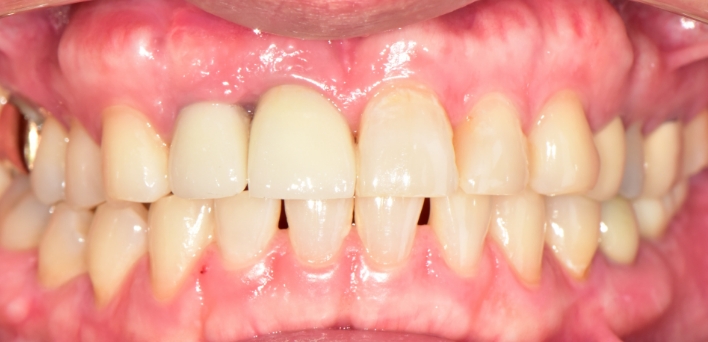

임플란트 : 손 ** 님 (50대)

치아가 있다는게, 아직도 정말 꿈만 같아요.

Before Before

2020.02.30

After After

※ 더서울치과의원은 의료법을 준수하며 위 케이스는 실제 환자의 동의를 얻은 사례로 치료 전, 후가 동일한 환경에서 촬영되었습니다.

환자 케이스에 따라 부작용이 발생할 수 있습니다. 이 부분은 의료진의 충분한 상담과 체크를 통해 예방하고 줄일 수 있습니다.

[임플란트 부작용] 수술 후 관리가 소홀할 경우 출혈, 주위염 등의 부작용이 발생할 수 있어 구강 위생을 철저히 유지하고, 정기적인 검진을 통해 상태를 점검하는 것이 중요합니다.

치아가 없어, 음식을 씹지 못했던 환자분

더서울이 당신의 저녁을 찾아드립니다

음식의 즐거움을 다시 느끼는,

나에게 꼭 맞는 컴퓨터 분석을 활용한 임플란트

더서울치과의원은 당신이 당신의 나이를 즐길 수 있도록, 당신의 저녁이 행복할 수 있도록

환자분의 마음을 이해하고, 맞춤 치료를 진행합니다.